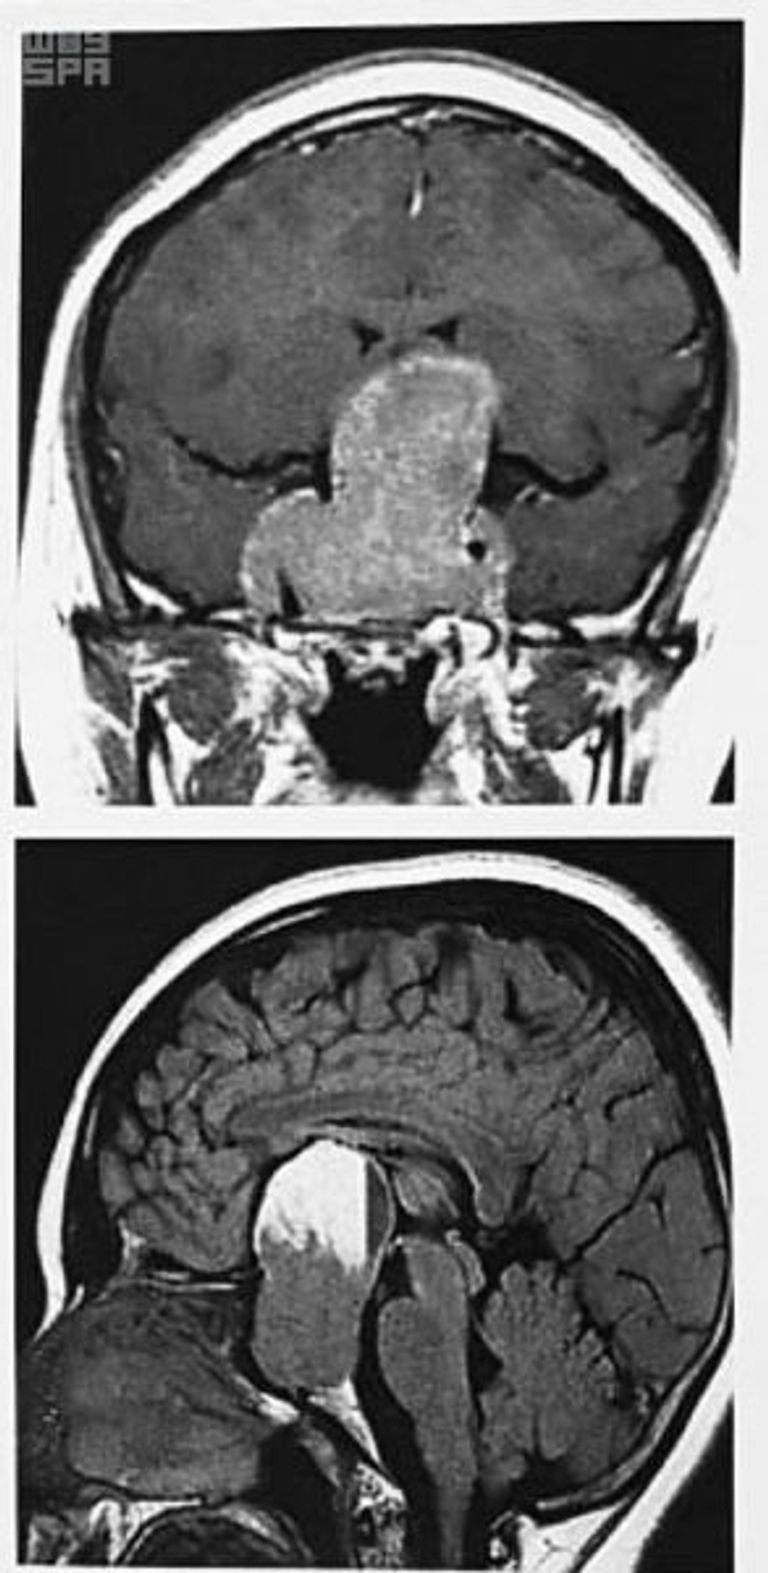

وتمحورت العملية حول استئصال ورم نازف في الغدة النخامية عن طريق الأنف.

وذكرت الإدارة الطبية أنّ المريضة، التي تبلغ من العمر 16 عاماً وأتت لأداء مناسك الحج مع والديها، أُحِيلت إلى المركز بعد فقدان شبه كامل للإبصار في العين اليسرى، وضعف شديد في العين اليمنى، نتيجة وجود ورم ضخم ونازف في الدماغ وتحديداً بالغدة النخامية، وضاغط على أعصاب العين.

واستأصل الفريق الطبي، المكوّن من استشاري جراحة المخ والأعصاب وقاع الجمجمة، الورم لتخفيف الضغط عن عصب العين، إثر عملية استغرقت 7 ساعات تكلّلت بالنجاح.